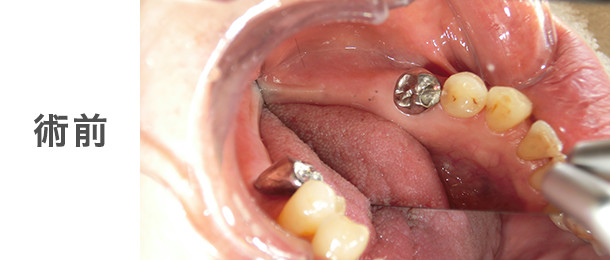

![]() |